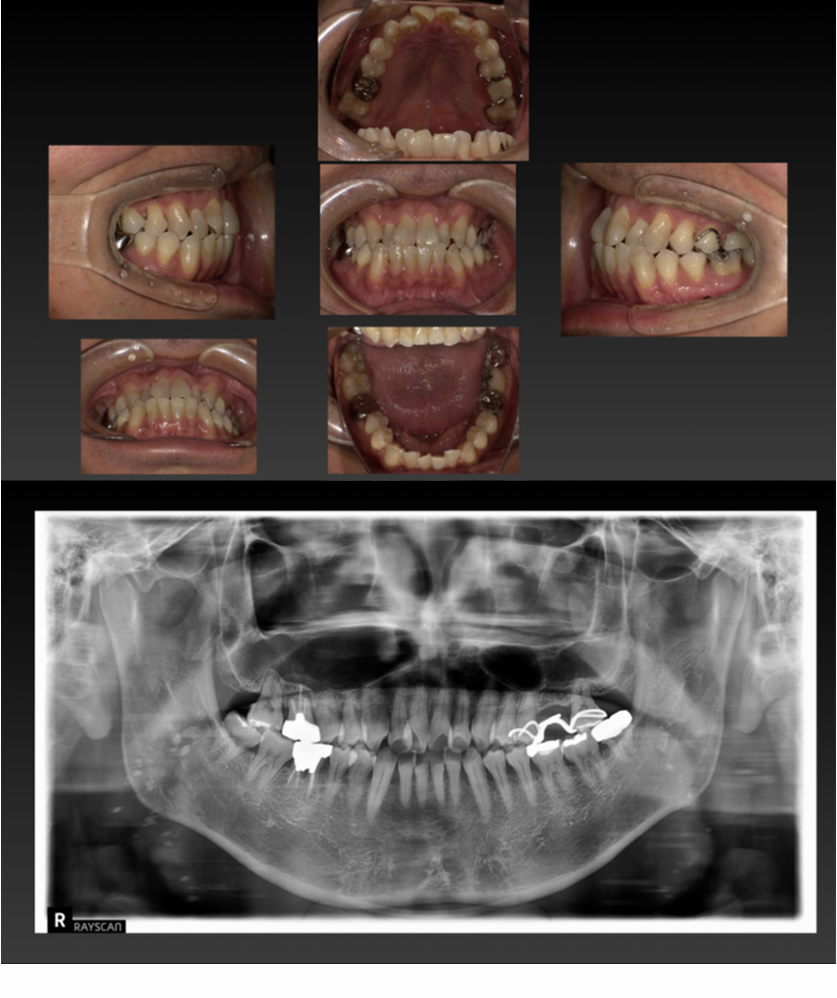

05 症例

歯が割れ、咬むと痛いのでインプラントにしたい

Before

After

| 治療内容 | 歯が割れていて咬むと痛いのでインプラント希望 |

| 患者さま | 60代女性 |

| 主訴 | 咬むと痛いのでインプラントにしたい |

| 治療期間(目安) | 3ヶ月 |

| 治療費(税込:目安) | ¥518,100 |

| リスク | 術後に多少の痛みや腫れが出ることがある。歯肉退縮がおきると、歯と歯肉の間に隙間が生じることがあります。 |